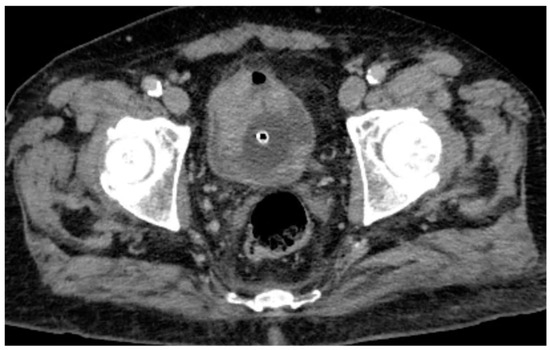

Following intravenous administration of iodinated contrast medium, the venous phase confirms the presence of the hyperdense lesions along the anterior and left posterolateral bladder walls, with potential contrast enhancement that cannot be unequivocally quantified (Figure 2). Consequently, conventional CT imaging alone was insufficient to definitively characterize the nature of these findings.

Figure 2. Venous phase CT scan confirms the previously described findings, showing a lesion involving the anterior and left posterolateral bladder wall, with an associated hyperdense intraluminal component.